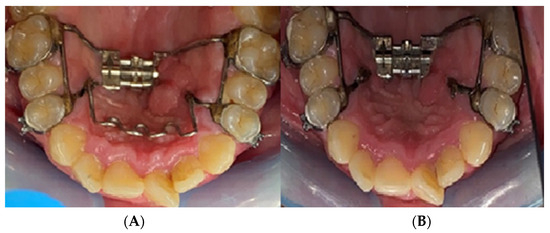

2.2. Palatal Expander Placement

2.3. Assessment of the Study Group